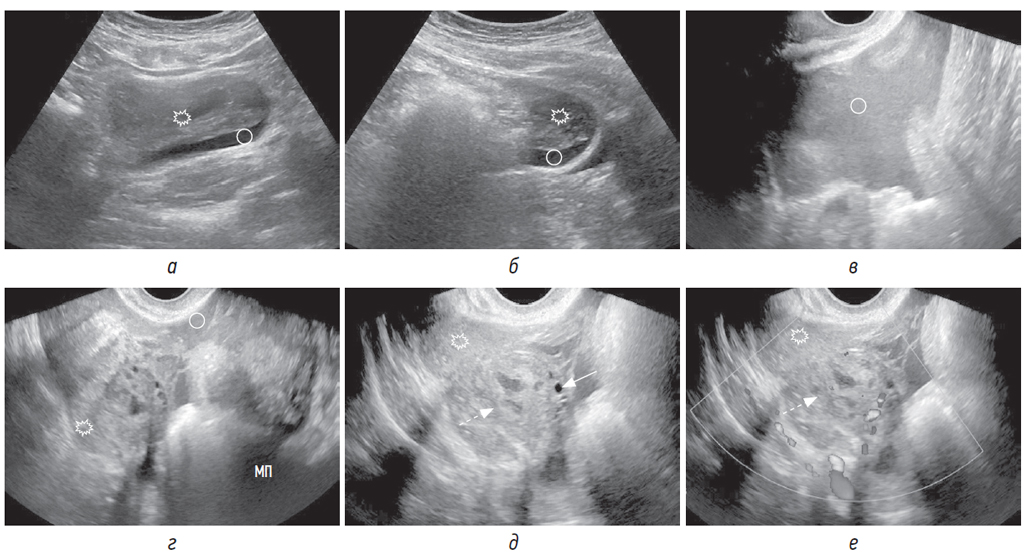

Гемоперитонеум при компьютерной томографии выявляется в виде свободной жидкости различной плотности, что позволяет на основании средних денситометрических показателей дифференцировать жидкую кровь (от +13 до +50 HU) от тромботических масс (от +50 до +75 единиц HU) (рис. 1, а–в) [1, 7–9]. Гемоперитонеум при эхографии может быть представлен однородно эхогенной жидкостью за счет равномерного распределения эхогенных частиц либо гетерогенной жидкостью за счет наличия сгустков крови (рис. 1, г–к; рис. 2, а–г), которые представляют собой хаотично расположенные структуры различной эхогенности, напоминающие солидную ткань на фоне эхогенной жидкости [4]. Сложности в выявлении сгустка возникают при изоэхогенности прилегающим структурам, что не позволяет диагностировать внутрибрюшное кровотечение.

Рис. 1. Пациентка 33 лет поступила с резкой болью в правой подвздошной области. В связи с подозрением на аппендицит была проведена нативная КТ. На КТ-томограммах в сагиттальной (а, б) и аксиальной (в) плоскостях в маточно-пузырном пространстве визуализируется жидкая кровь (круг) и сгусток (звездочка), прилежащий к кистозному образованию (пунктирная стрелка) в правом яичнике; в маточно-прямокишечном пространстве — жидкая кровь (стрелка). При трансвагинальном УЗИ по длинной оси матки (г) визуализируется жидкая кровь в маточно-прямокишечном пространстве (стрелка) и сгусток в маточно-пузырном пространстве (звездочка). На серии трансвагинальных сонограмм в В-режиме (д–к) и с использованием ЦДК (е) в правом яичнике определяется кистозное образование (пунктирная стрелка) с толстой и гиперваскулярной стенкой, с геморрагическим содержимым, с наличием параовариально эхогенной крови (круг) и сгустков крови (звездочка). Предполагаемое место разрыва показано между стрелками на сонограмме (л) и соответствующей нативной КТ-томограмме в аксиальной плоскости (м)

При КТ и УЗИ именно наличие тромботических масс помогает отличить кровь от экссудата и транссудата.

При КТ и УЗИ важно определить локализацию сгустка, которая, как правило, указывает на источник кровотечения. Так называемый «сторожевой сгусток» тесно прилежит к травмированному яичнику непосредственно в месте разрыва (рис. 1, а–в, д–м; 2, д–е; 3, г–е). В случае продолжающегося кровотечения сгусток может быть больших размеров и охватывать яичник на большом протяжении, что затруднит локализацию места предполагаемого разрыва в яичнике.